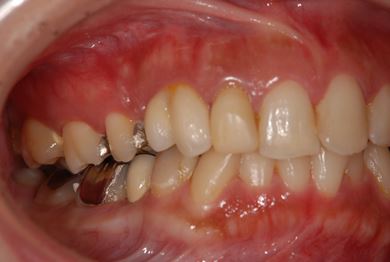

インプラントの症例写真 IMPLANT

抜歯即日スピードインプラント治療

| 性別/年齢 | 女性 / 29歳 | ||||||||||||||||||||||||||||||||

| 主訴 | 以前治療中のままだった部位の歯の根に膿が溜まって、痛みと腫れが出た。応急処置で切開して膿は取ってもらったが、根の治療がまだなので、お願いしたい。 | ||||||||||||||||||||||||||||||||

| 治療方針 | 抜歯と同時にインプラント埋入を行い、治療期間を短縮する。 | ||||||||||||||||||||||||||||||||

| 治療内容 | インプラント2本(抜歯即日スピードインプラント)、ハイブリッドセラミッククラウン3本 | ||||||||||||||||||||||||||||||||